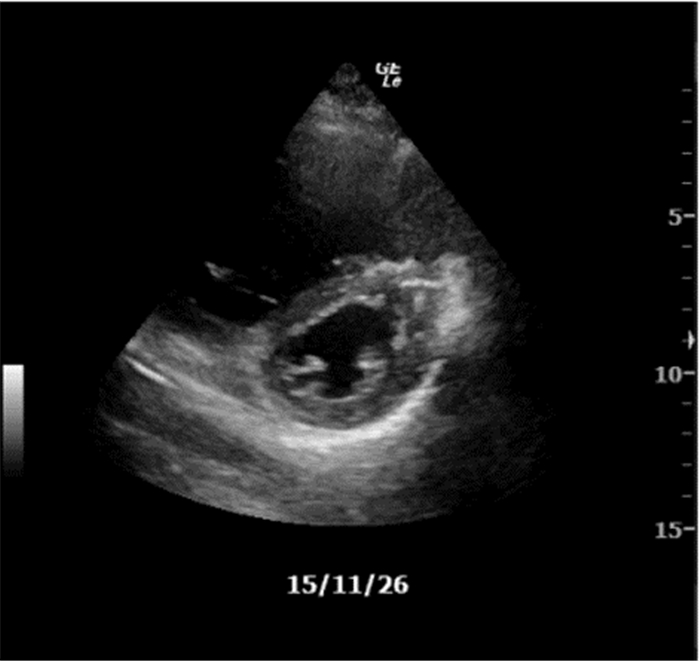

2.2.2 胸膜滑动征消失M型超声下因肺滑动消失而导致“沙滩征”被“条码征”取代(图 10),多见于气胸患者,单纯胸膜滑动征消失还可见于呼吸暂停、肺不张、右主支气管插管或胸膜粘连患者。

即“沙滩征”与“条码征”的交点(图 10),提示气胸诊断。